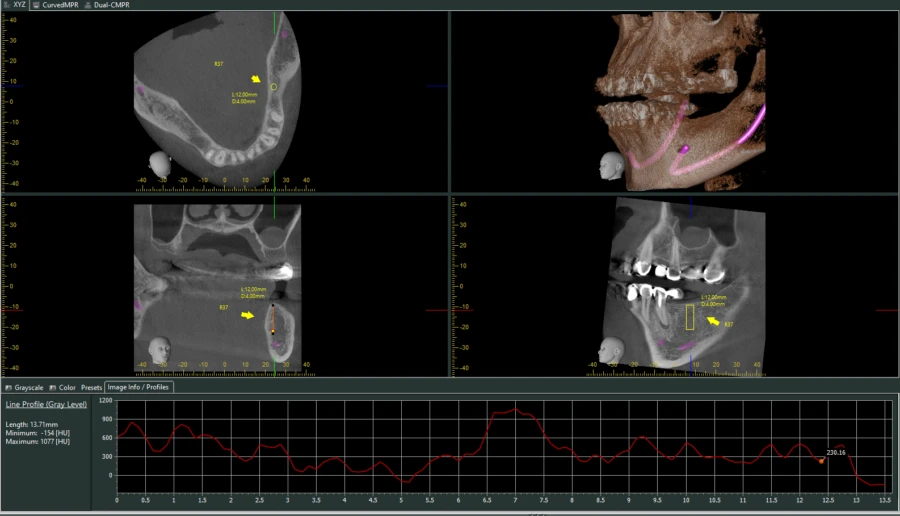

Điều đặc biệt của HU đối với thiết bị CBCT

Ứng dụng của HU trong CBCT rất quan trọng, chẳng hạn, khi khảo sát phim của một Implant mới cấy, đường đồ thị thể hiện chất lượng xương (HU) từ lớp xương vỏ, cắt ngang qua thân Implant có thể dễ dàng cho thấy sự tích hợp của xương quanh thân Implant đó như thế nào.

Riêng với Morita, chỉ số được thể hiện chính xác, và bạn hoàn toàn có thể tin cậy chỉ số này để đánh giá chất lượng, mật độ xương.

Bạn có thể tự mình kiểm chứng điều này khi sử dụng thang đo Profile trên các phần mềm CBCT (hay thang HU trên phần mềm i-Dixel Morita).

Các nha sĩ sẽ có được những con số chính xác và sát thực khi đo mật độ xương thông qua phần mềm i-Dixel. Từ đó, những trường hợp có HU nằm trong cấp độ D2, D3 sẽ thích hợp cho việc cắm Implant. Kết hợp khám lâm sàng và nhiều yếu tố khác, các nha sĩ hoàn thành ca cấy ghép một cách hoàn hảo và đảm bảo độ tích hợp xương sau điều trị.